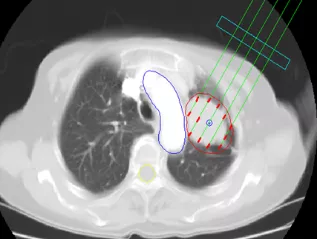

放射性粒子植入(粒子植入肿瘤内持续”照射“灭活肿瘤)

肿瘤粒子植入:是将放射性粒子精准植入肿瘤内,让其持续释放出射线,以摧毁肿瘤的治疗手段。通过照射可使肿瘤细胞DNA断裂,使肿瘤逐渐萎缩。